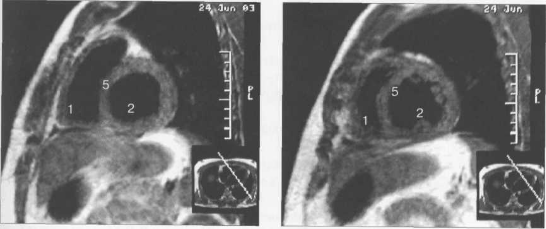

КТ-исследование позволяет получать поперечные (аксиальные) сечения сердца. Стандартная пошаговая КТ и даже спиральная КТ не получили распространения для исследования морфологии и функции сердца. Более тщательный анализ внутрисердечных структур возможен с помощью многослойной спиральной КТ (МСКТ) в условиях внутривенного контрастирования. КТ-изображения сердца и сосудов на различных уровнях представлены на рис. 9.34.

Рис. 9.34. КТ сердца и сосудов.

1 — правый желудочек; 2 — левый желудочек; 3 — правое предсердие; 4 — левое предсердие; 5 — межжелудочковая перегородка; 6 — межпредсердная перегородка; 7 — верхняя полая вена; 8 — восходящая часть аорты; 9 — нисходящая часть аорты; 10 — легочный ствол; 11 — правая легочная артерия; 12 — диафрагма; 13 — легочные вены.